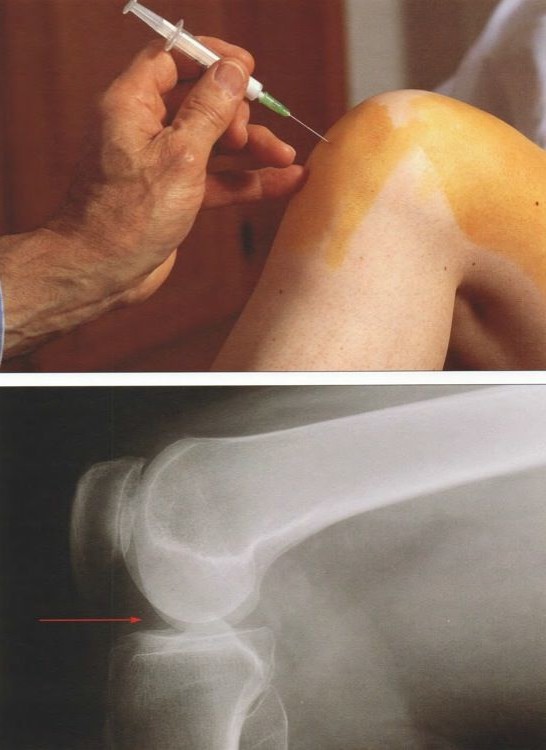

Для того чтобы правильно назначить лечение и устранить причину развития заболевания проводят специальную диагностику. Она направлена по большей части на выявление основного заболевания. Вначале делают рентгенографию, а после артроскопии УЗИ и МРТ коленного сустава. Дальше проводят пункцию для забора суставной жидкости. При острой и инфекционной формах синовита колено предварительно обезболивают. После артроскопии отправляют на исследование и выполняют посев.

Пункция коленного сустава проводится быстро и несложно. В суставную полость погружают тонкую иглу и берут незначительное количество жидкости. После этого в сустав вводится антибиотик в обязательном порядке, чтобы остановить воспаление и предотвратить развитие инфекции (если синовит асептический).

Фотогалерея «Лечение и диагностика синовита»

- Забор суставной жидкости

Видео «Лечение синовита»

В видео показано как происходит лечение синовита коленного сустава. Здесь подробно изображен процесс пункции.